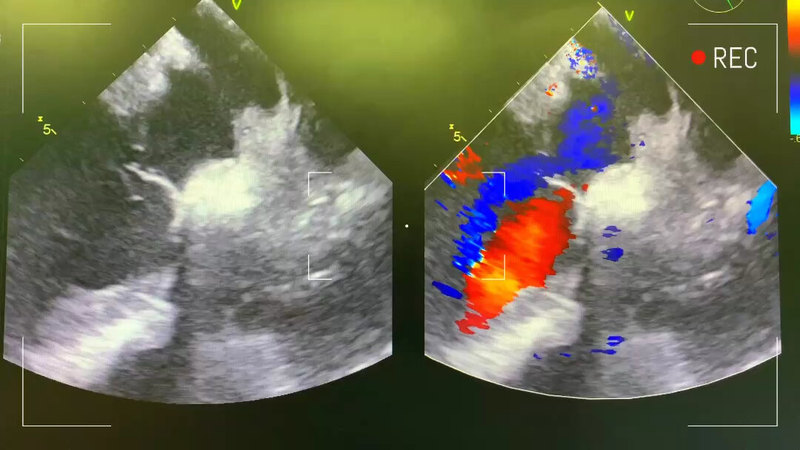

治療前患兒出生18天就診,當(dāng)時(shí)呼吸急促,雙下肢水腫,吃奶費(fèi)力。ct和b超診斷先天性心臟病,主動(dòng)脈狹窄,室間隔缺損治療中手術(shù)為體外循環(huán)下主動(dòng)脈狹窄矯治+室缺修補(bǔ)術(shù)治療后治療后7天術(shù)后心超復(fù)查恢復(fù)良好,患兒心功能和肺動(dòng)脈高壓明顯好轉(zhuǎn)。準(zhǔn)備2.27出院